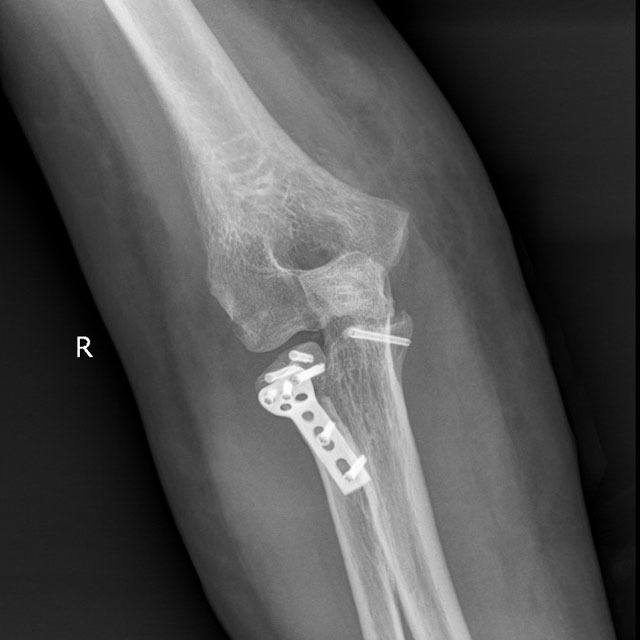

术前影像

骨伤科创伤·正骨组医生接诊后,迅速组织多学科专业医疗团队进行详细检查和诊断,确诊为肘关节骨折脱位,并立即制定了周密的手术计划。